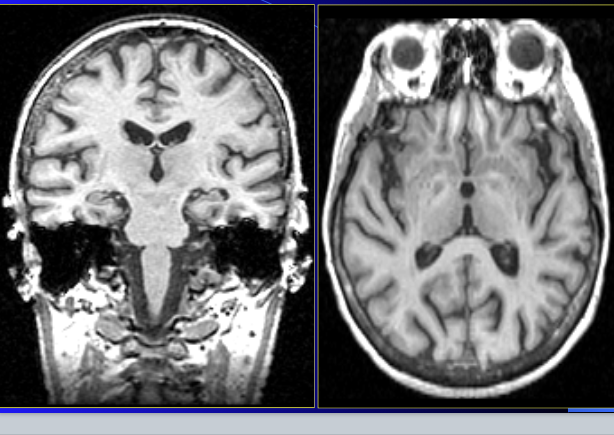

is this MRI, CT, XRay…

at what level?

CT

left: lateral ventricles so it is very superior

right: brainstem level (the eyeballs are present)